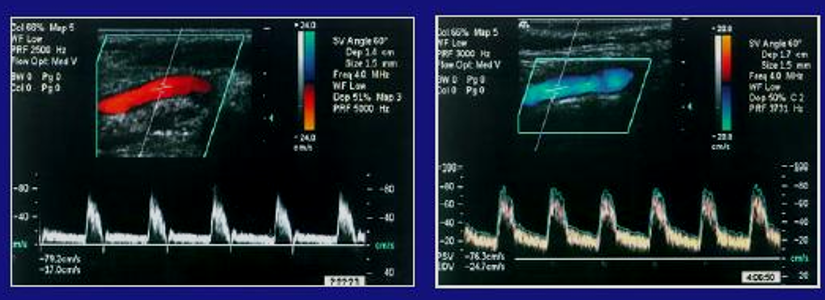

Based on the waveforms, which vessel do they belong to?

CCA

True or False: The picture on the left shows an ICA flow pattern

False

True or False: The picture on the left shows an ECA flow pattern

True